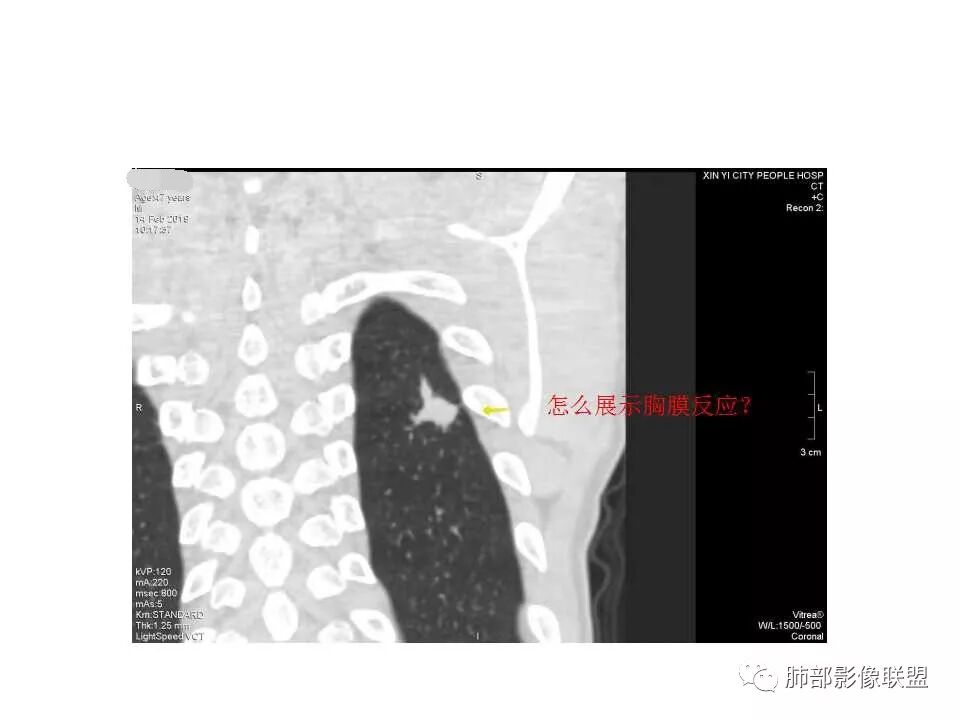

考虑结核,左肺下叶病灶,强化不明显,胸膜反应性增厚,有卫星灶,强化不明显。

影像:病灶不规则,形态奇特,矢状位可能看到病灶的真实形态;上面近端病灶似乎与主病灶不相连续,多病灶?内侧似乎小花小草,疑为卫星灶;胸膜下病变,与胸膜关系不密切,胸膜线状强化;强化方式渐进性,感觉不均匀,也许是伪影;病灶凹陷平直不膨隆,考虑良性。诊断:结核;鉴别:腺癌(近胸膜端三个胸膜反应凹,偏上部层面毛刺不能除外,但其他地方没有,整体收缩力还比较弱,无钙化,考虑没有形成钙化和纤维化。

我会做一做支气管的CPR,肺动脉的CPR。

因为南边的考虑一定要看到支气管,怎么办呢?

我很早以前做早癌,就是用CPR技术来观看病灶与支气管、血管的关系。

我的重建图像大部分是这样。

360旋转,可以观看意想不到的效果,我一直很重视这两种重建方法。比想象好 直观。